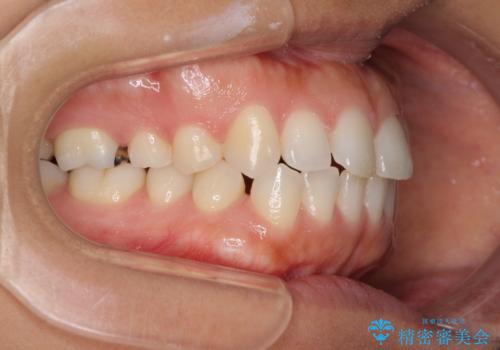

受け口傾向の前歯 すきっ歯の改善

- 前歯の隙間と口元の突出感を気にして来院された患者様です。

嚥下時に舌を突出させる癖があり、成長期に下顎が有意に成長し、歯と歯の間に隙間ができてしまいました。

舌の癖を改善し、インビザラインにて治療を行うこととしました。

舌癖を改善したことで、隙間や突出感を改善することができました。

隙間は後戻りしやすいため、舌側を細いワイヤーで固定することとしました。